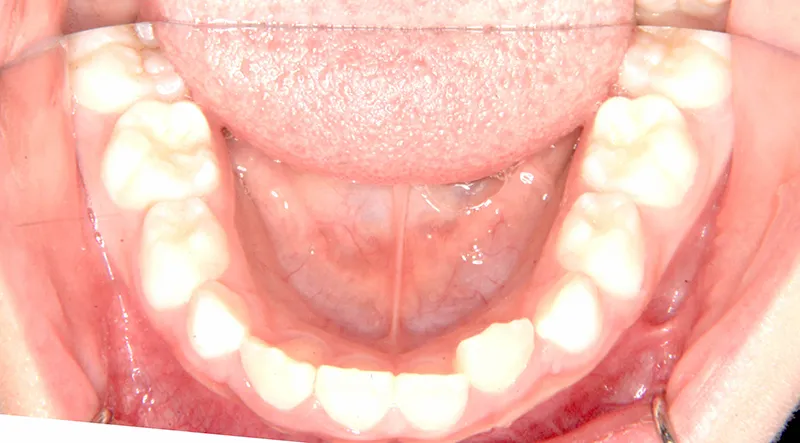

【子供の矯正(一期)】叢生・反対咬合・受け口・非抜歯症例・7歳女児【M.H様】

初診時年齢 小学校1年生 (女性) 主訴 受け口

診断名 叢生・反対咬合 装置名

状態 永久歯が生える隙間がない(叢生)

受け口(下顎前突/反対咬合)

下顎が大きい傾向があります。

上下の真ん中にズレがあるのと、上下とも永久歯の生えるスペースがせまいため、オリジナル矯正装置でスペースを作り、受け口も改善していきます。

初診